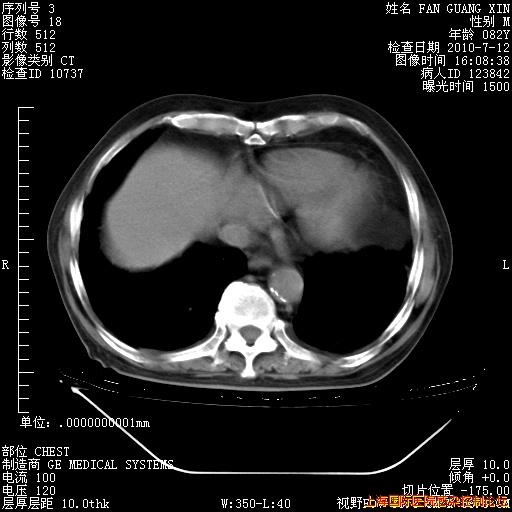

今天复查CT

今天CT

整整相隔30天的肺部CT好像有所好转啊。甲强龙减量第3天,需要观察体温。